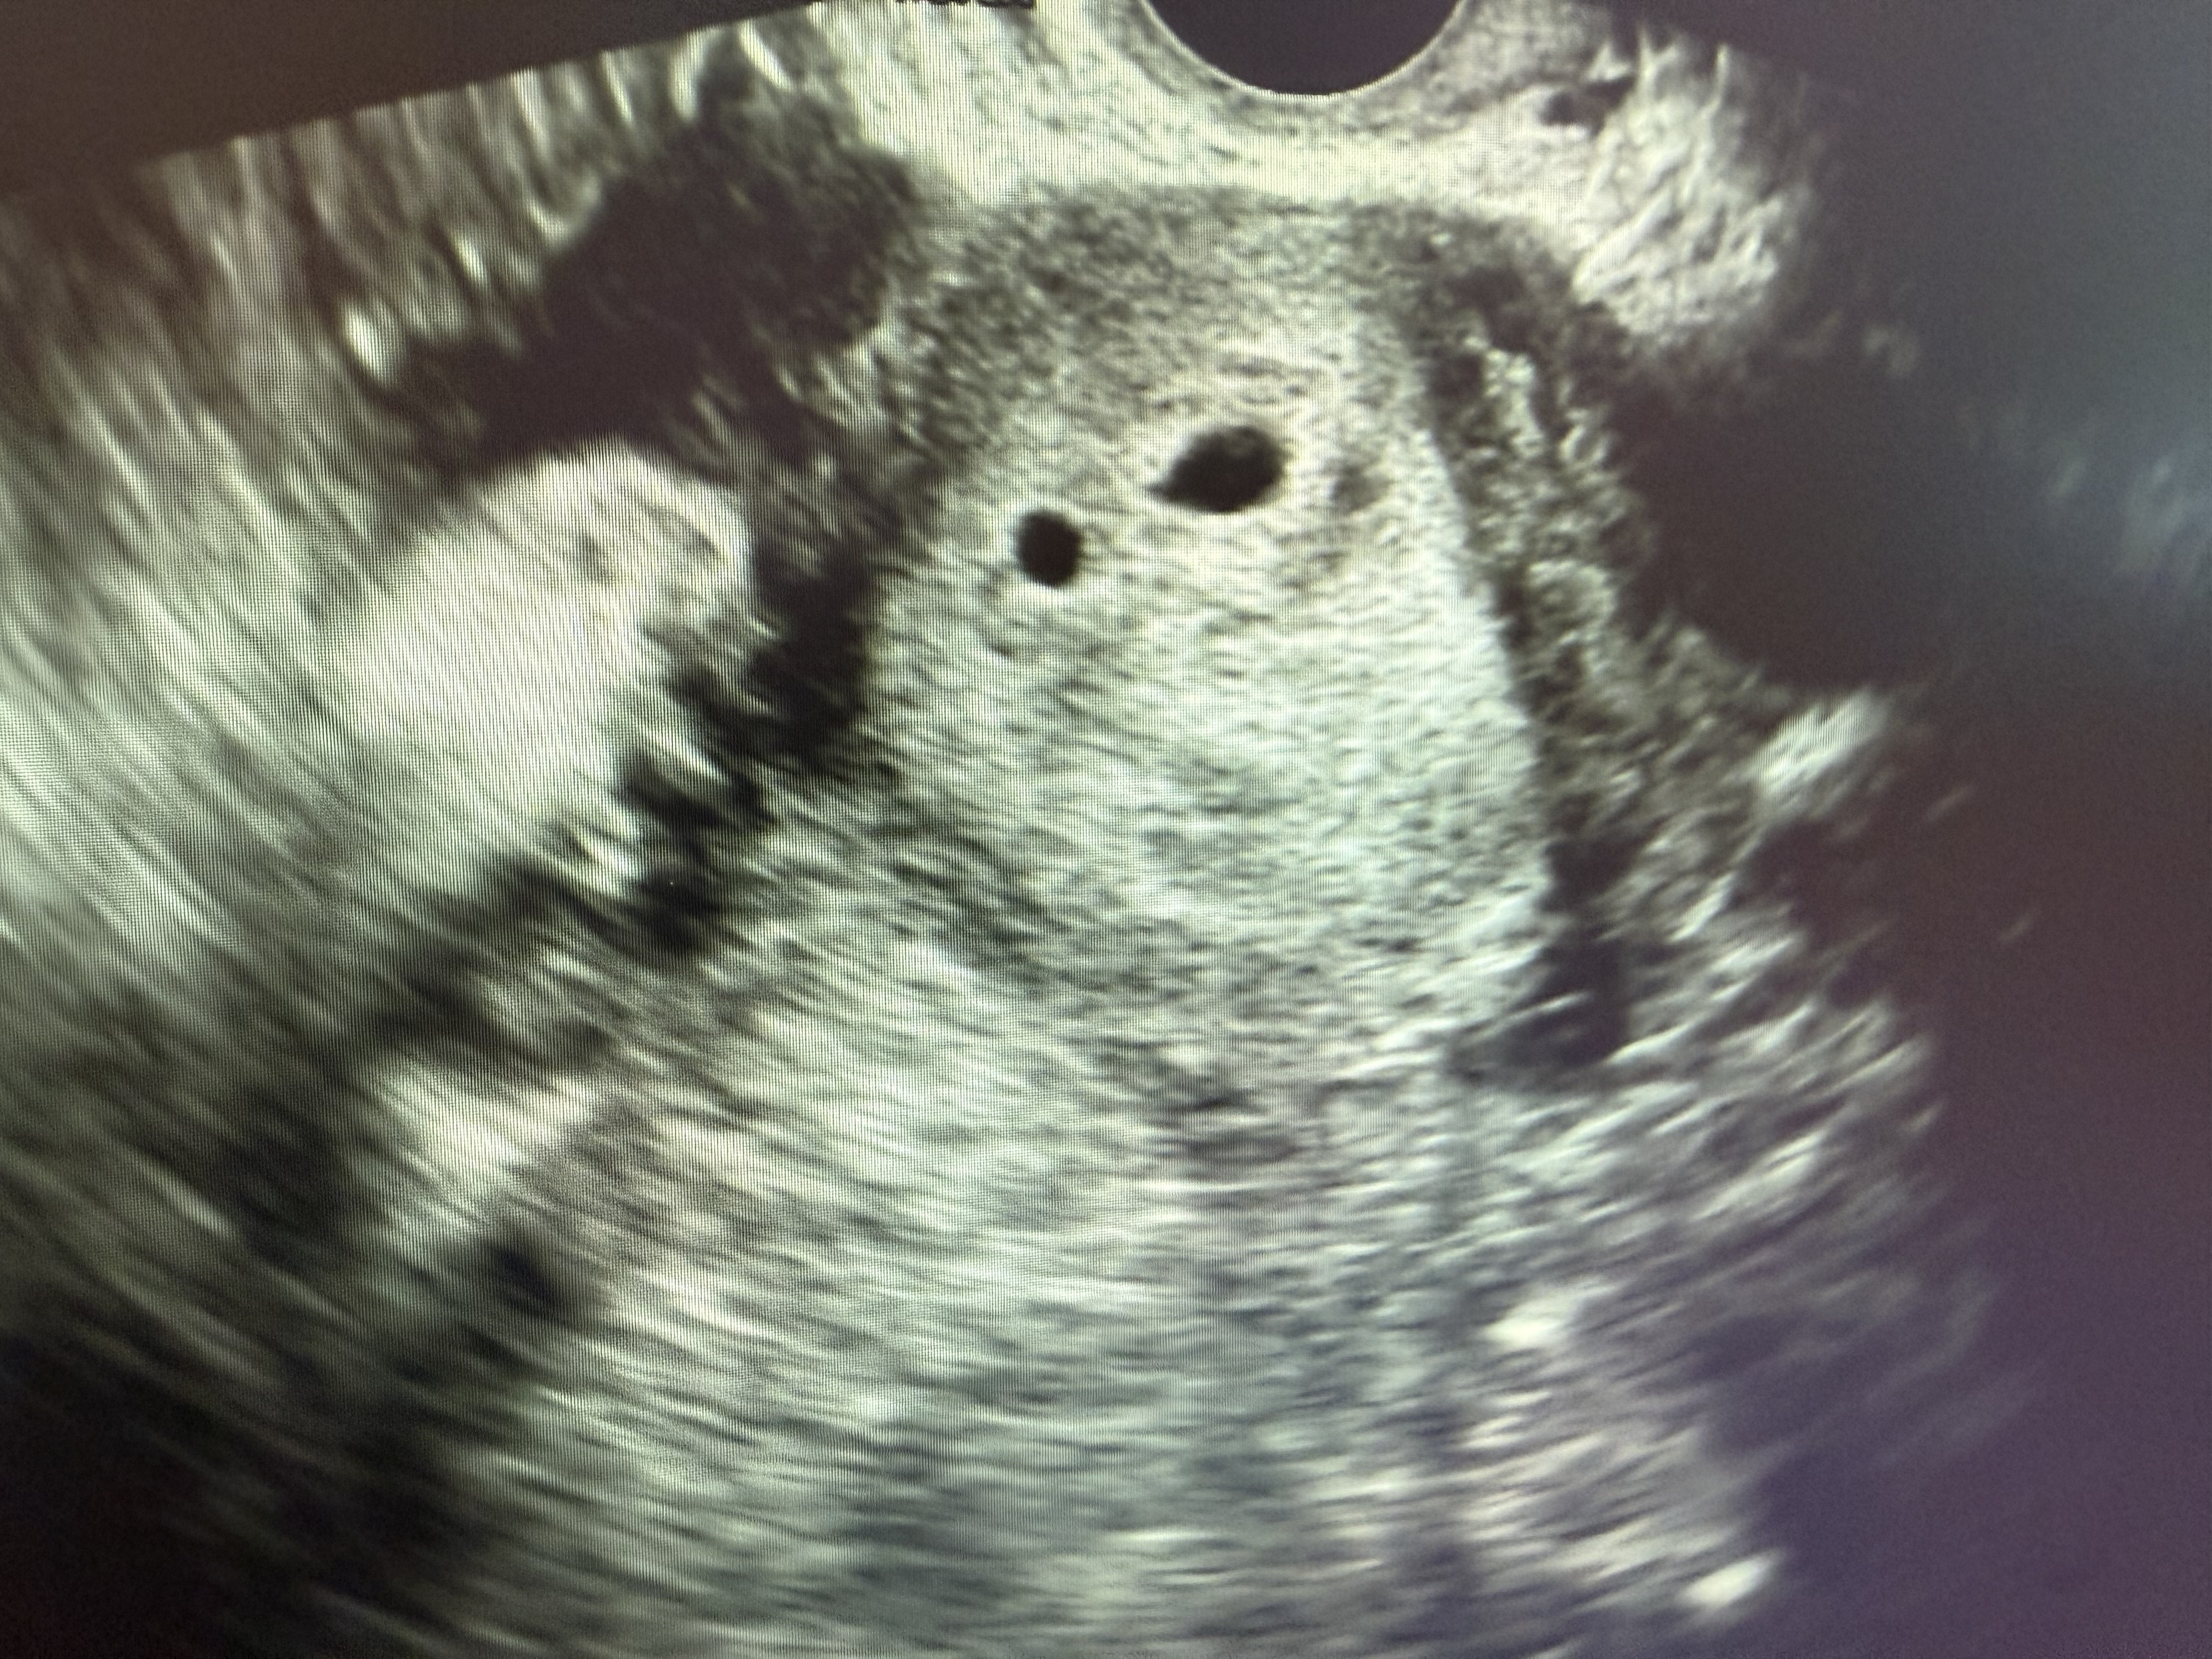

쌍둥이일까용?

오늘 4주6일차로 처음 초음파봤어요!! 한명은 확실한데 아기집인지아닌지 애매한게 하나더보인다고 쌍둥이가능성도 있다해서요 배란유도제 먹고 난포두개자라고 난포터지는주사맞고 임신된케이스라 초음파한번봐주세용